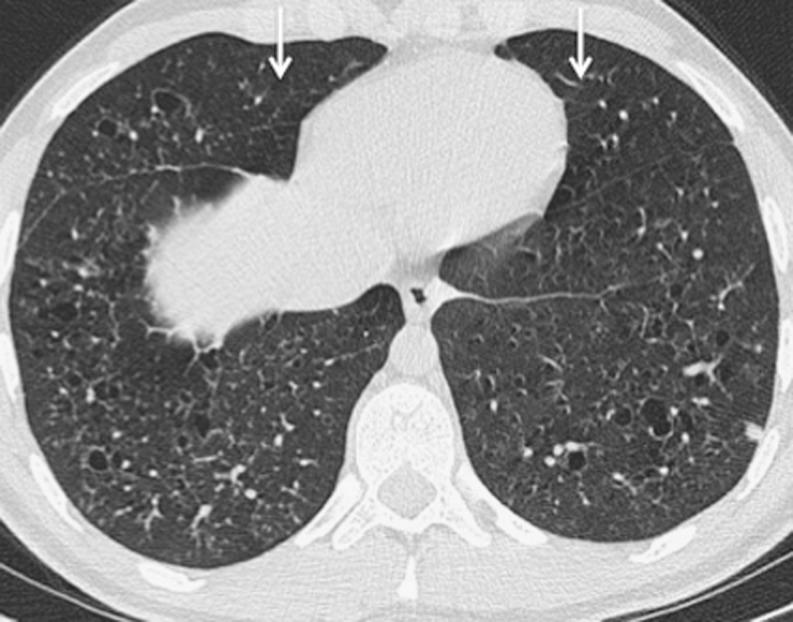

A lung cyst is defined as a round parenchymal lucency or area of low attenuation with a thin wall. They are not uncommon findings on high-resolution (HR) thoracic computed tomography (CT) and when identified, they require explanation. The differential diagnosis for diseases characterised by lung cysts is broad ranging from isolated chest disorders to rare multisystem diseases. This article provides a practical approach for evaluating lung cysts on HRCT, highlighting disorders in which the HRCT findings can be diagnostic as well as conditions where correlation with clinical history or biopsy is required.

肺囊肿被定义为圆形的实质透亮区或具有薄壁的低衰减区域。它们在高分辨率(HR)胸部计算机断层扫描(CT)上并非罕见的发现,一旦被识别,就需要进行解释。以肺囊肿为特征的疾病的鉴别诊断范围广泛,从孤立的胸部疾病到罕见的多系统疾病。本文提供了一种在HRCT上评估肺囊肿的实用方法,重点介绍了HRCT表现具有诊断价值的疾病以及需要结合临床病史或活检的情况。